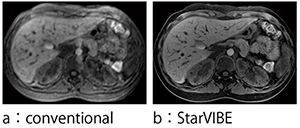

図2 StarVIBEと従来法の比較

StarVIBEは,VIBE法にラジアルサンプリング法を応用することによって,動きに強い3D造影撮像を行うことを目的としている。k-space上のラジアルサンプリングによる動き補正の効能は広く知られているが,3D造影撮像に応用することで,さまざまな状況下での造影検査を可能にする。特に,小児検査やご高齢の方の検査などで息止め管理が難しい状況下でも,安定して造影検査が行えるよう考えられた。撮像時間は2〜3分程度で(被検者の状態により異なる),息止めのない自由呼吸下での造影検査が可能になり,モーションアーチファクトが大幅に低減された高画質な平衡相の造影画像の取得が可能である(図2)。